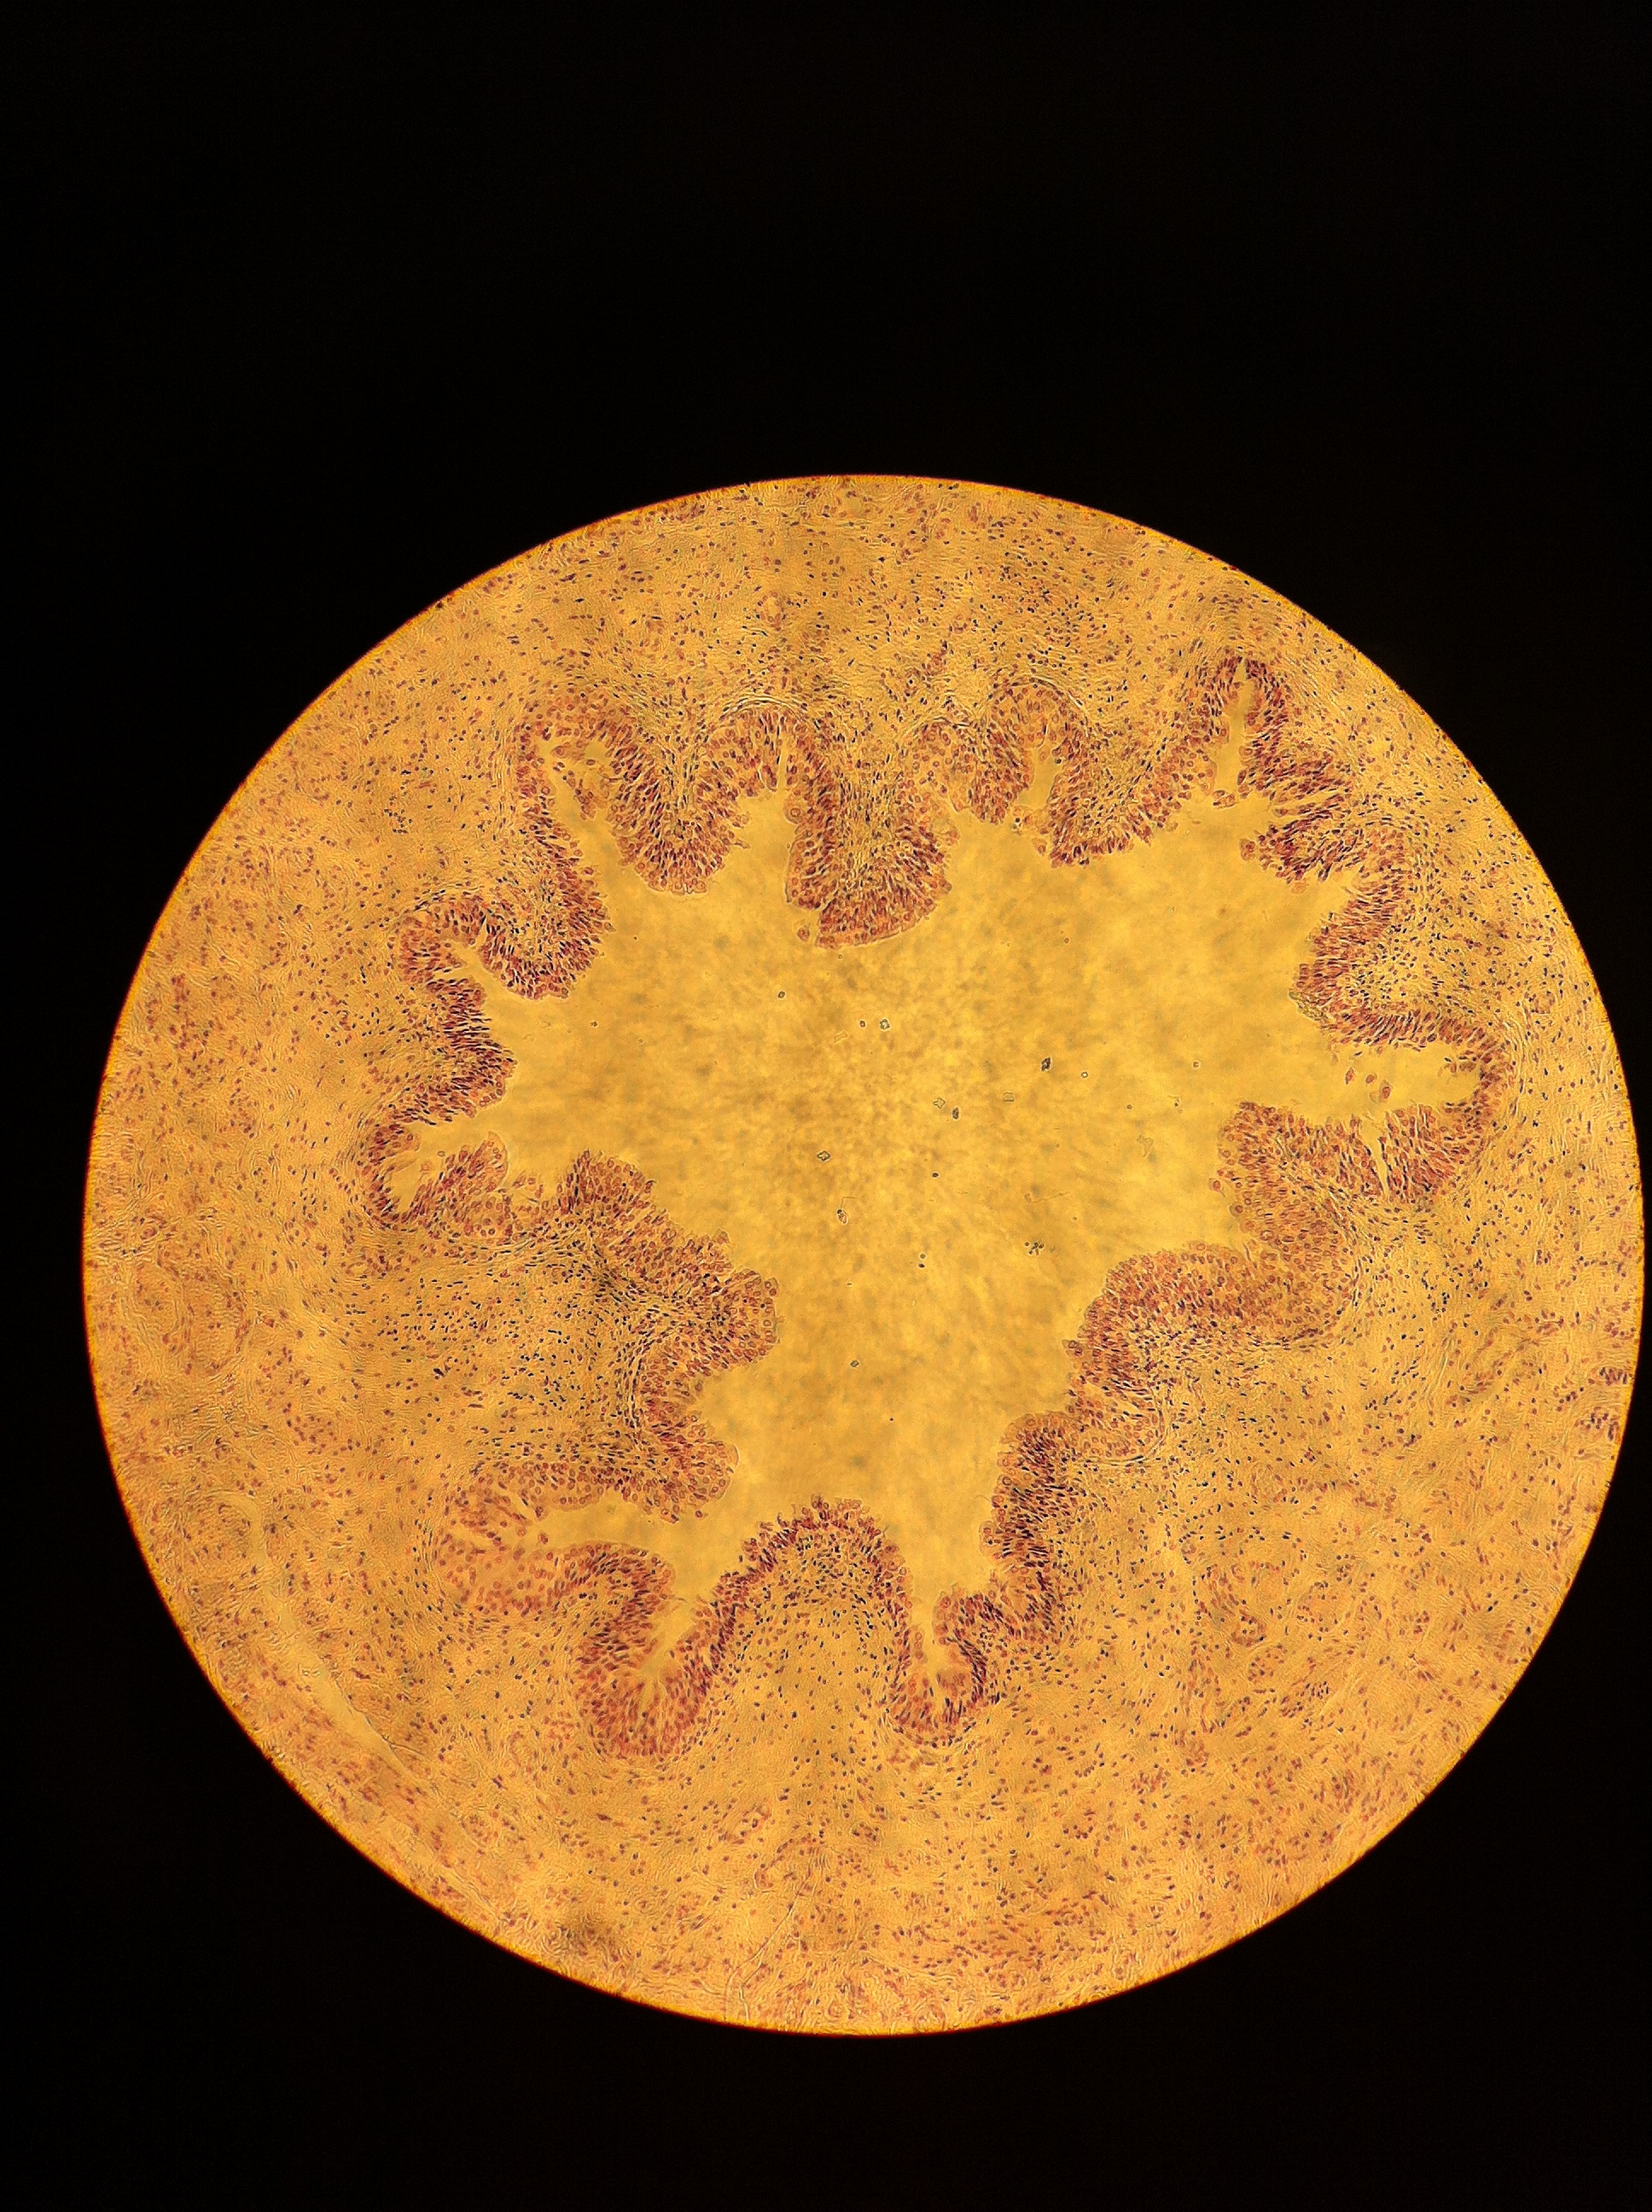

Ureter 40X

Ureter 100X